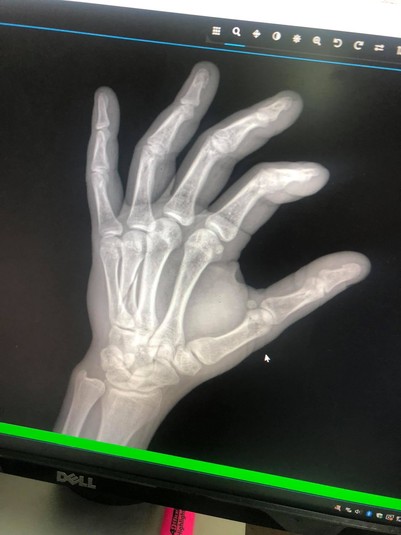

Фото Facebook Ірини Федорченко

В результаті побиття чоловік отримав перелом руки зі зміщенням, а діти серйозну психічну травму

Потерпілий Андрій Федорченко показав наслідки інциденту на НСК «Олімпійський».